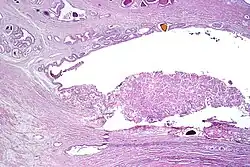

Intraductal carcinoma

Intraductal carcinoma of the prostate gland (IDCP), which is now categorised as a distinct entity by WHO 2016, includes two biologically distinct diseases. IDCP associated with invasive carcinoma (IDCP-inv) generally represents a growth pattern of invasive prostatic adenocarcinoma while the rarely encountered pure IDCP is a precursor of prostate cancer.[20] The diagnostic criterion of nuclear size at least 6 times normal is ambiguous as size could refer to either nuclear area or diameter. If area, then this criterion could be re-defined as nuclear diameter at least three times normal as it is difficult to visually compare area of nuclei.[20] It is also unclear whether IDCP could also include tumors with ductal morphology.[20] There is no consensus whether pure IDCP in needle biopsies should be managed with re-biopsy or radical therapy. A pragmatic approach would be to recommend radical therapy only for extensive pure IDCP that is morphologically unequivocal for high-grade prostate cancer.[20] Active surveillance is not appropriate when low-grade invasive cancer is associated with IDCP, as such patients usually have unsampled high-grade prostatic adenocarcinoma.[20] It is generally recommended that IDCP component of IDCP-inv should be included in tumor extent but not grade.[20] However, there are good arguments in favor of grading IDCP associated with invasive cancer.[20] WHO 2016 recommends that IDCP should not be graded, but it is unclear whether this applies to both pure IDCP and IDCP-inv.[20]

-

Intraductal carcinoma of the prostate with an infiltrative growth pattern may be morphologically difficult to distinguish from invasive cancer. One focus shows comedonecrosis (arrow), morphologically suggesting Gleason pattern 5 invasive carcinoma (a haematoxylin and eosin, b CK5/6)[20] -

Intraductal carcinoma of the prostate with very patchy basal cells identified by immunohistochemistry. At least some of the glands lacking basal cell immunoreactivity represent intraductal rather than invasive carcinoma (a haematoxylin and eosin, b CK 5/6)[20]

Ductal adenocarcinoma may have a prominent cribriforming architecture, with glands appearing relatively round, and may thereby mimic intraductal adenocarcinoma, but can be distinguished by the following features:[10]

| Feature | Ductal adenocarcinoma | Intraductal adenocarcinoma |

|---|---|---|

| True fibrovascular cores in micropapillary architecture | Present | Usually absent |

| Cribriform lumens | Lined by pseudostratified, columnar cells | Punched out lumens lined by cuboidal cells |

| Basal cell markers | Usually negative | Usually positive |